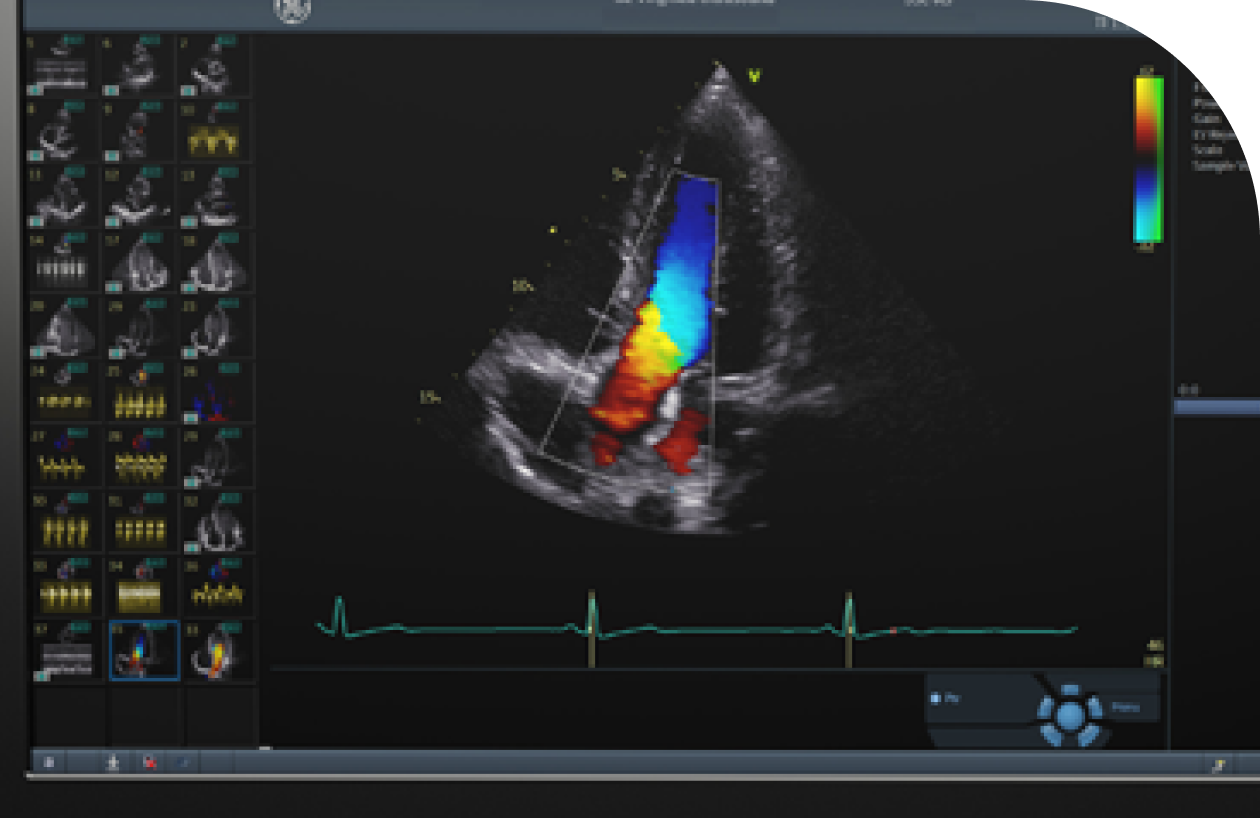

심혈관검사

경동맥초음파

동맥 경화는 뇌졸중, 심근경색 등을 유발할 위험이 높아

조기발견하고 진행을 예방하는 것이 중요

• 동맥경화와 혈관 협착 여부를 확인하고 조기 예방과 치료 계획 수립에 도움을 주기 위함

• 경동맥에 초음파 탐촉자를 대어 혈관 내벽과 혈류 상태를 관찰하는 비침습적 검사